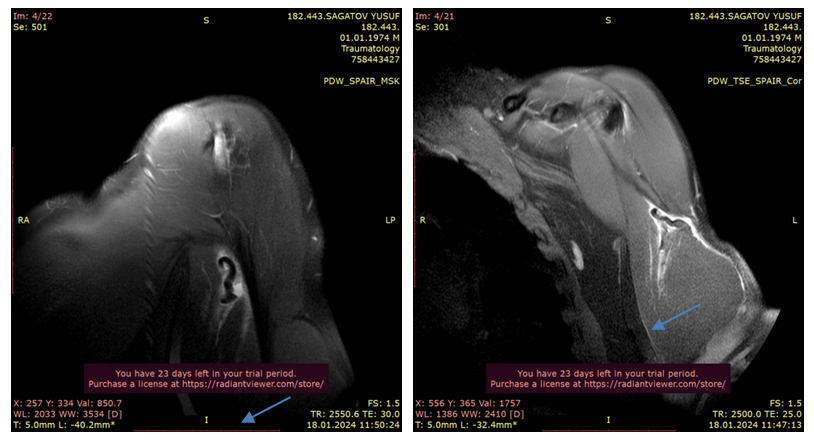

Clinical Case. Patient S.Yu., born 1974. Case No. 738/2024.The patient presents with complaints of pain and deformity in the left shoulder area. Medical history: On 14.01.2024, during a football training session, a "popping" sound was heard. After 2 days, pain, swelling, and deformity appeared. The patient underwent standard examination procedures and was diagnosed with: Rupture of the long head tendon of the left biceps brachii muscle. On 19.01.2024, the patient underwent surgical procedure No. 171 "Fixation of the long head tendon of the left biceps muscle."Ultrasound examination provided the following conclusion: Echo signs of rupture of the long head tendon of the biceps brachii muscle with hematoma formation, and tendinopathy of the rotator cuff tendons of the left shoulder joint are detected.Radiological examination revealed signs of primary osteoarthritis in the acromioclavicular joint. | Figure 2. Patient S.Yu. X-ray analysis |

| Figure 3. Patient S.Yu. MRI analysis |